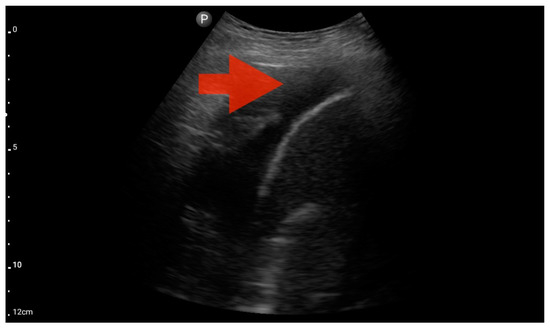

Left ventricle hypokinesis; position: apical four-chamber (FATE protocol). Sector probe; the red arrow marks the left ventricle, which, during the examination, showed signs of reduced ejection fraction and hypokinesis (source: author’s material—DK).

Figure 13.